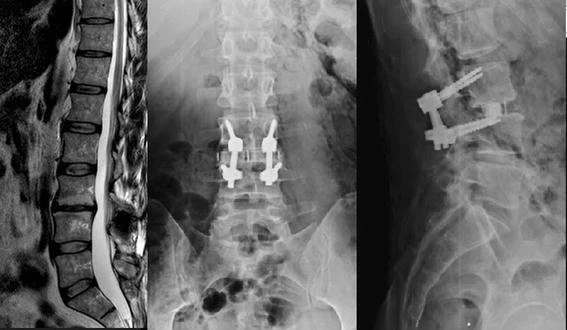

MRI của dụng cụ cố định cột sống

Những bệnh nhân đã phẫu thuật đặt các thiết bị kim loại vào cột sống, chẳng hạn như vít cuống sống hoặc lồng nhân tạo, có thể được chụp MRI dưới sự giám sát, nhưng độ phân giải của lần chụp thường bị nhiễu nghiêm trọng bởi thiết bị kim loại và chất lượng của nghiên cứu hình ảnh kém.

Nhìn chung, thiết bị cấy ghép bằng chất liệu thép không gỉ gây ra mức độ nhiễu hình ảnh nghiêm trọng hơn bằng titan. Titan là vật liệu thuận từ thường không bị ảnh hưởng bởi từ trường của MRI. Vì lý do này, titan đã trở nên phổ biến trong dụng cụ cố định cột sống và thép không gỉ phần lớn không được ưa chuộng do không thể chụp MRI rõ nét sau phẫu thuật.